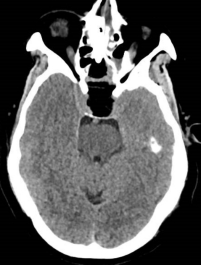

脑膜瘤术前核磁 术后CT